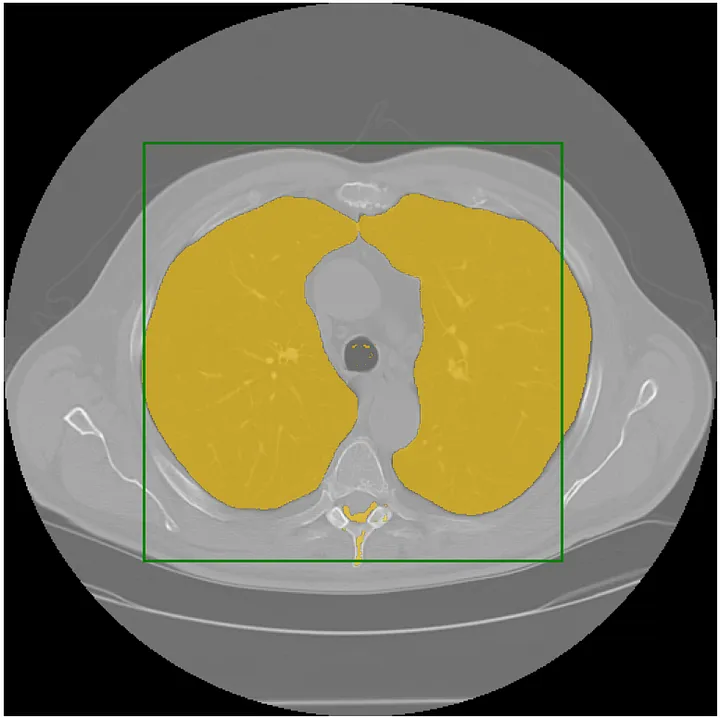

| Segment Anything Model for Medical Image Analysis: an Experimental Study | ![]() |

arXiv | - | - | - | Thorough experiments evaluating how SAM performs on 19 medical image datasets. |

| SAM-Med2d | ![]() |

arXiv | - | Code | Sichuan University & Shanghai AI Laboratory | The most comprehensive studies on applying SAM to medical 2D images |